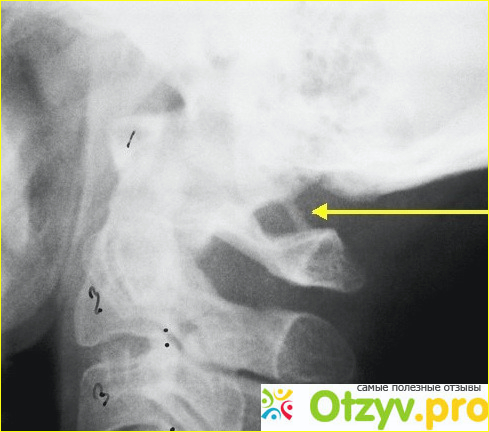

Окостенение боковой части задней атланто-затылочной мембраны имеет тенденцию охватывать позвоночную артерию в отверстии, ограниченном спереди суставной гранью С1, ниже по канавке для позвоночной артерии на верхней поверхности задней С1-арки и позади сама окостененная мембрана.

Это называют по-разному - ponticulus posticus (латинский для малого заднего моста), дугообразным отверстием, ретроартикулярным или ретрокондилярным отверстием, аномалиями Киммерле, отверстием сагиттального кольца или ретрондикальным позвоночным кольцом. Травственное исследование показало, что его заболеваемость составляет 13,8%.

Наличие этого отверстия связано с хроническими головными болями напряжения и сенсоневральной потерей слуха, а также болью в руках, болью в шее и головокружением. Такая проблема также является причиной рассечения позвонков и появления инсульта у детей из-за привязки позвоночной артерии внутри него. Данное отверстие можно легко идентифицировать на предоперационных рентгеновских лучах или парасагиттальных КТ-срезах, и тщательное изучение изображений важно для того, чтобы начать лечение во время. Сосудистые аномалии возникают, когда артерии, вены, капилляры или лимфатические сосуды не развиваются должным образом. Некоторые из них могут обезображивать, а некоторые могут представлять опасность для здоровья. Многие сосудистые аномалии врожденны (присутствуют при рождении), но другие могут развиваться позже в жизни ребенка.

Атлант это уникальный позвонок по своему строению. Данный позвонок не имеет тела, а состоит их дуг. В задней дуге данного позвонка есть углубление, и через него проходит нерв спинномозговой, а также артерия позвоночная. Если костные ткани, которые образую борозду на артерии спинномозговой разрастается очень сильно, то сама выемка в размере становится меньше. Киммерле представляет собой перерождение борозды на задней дуге атланта в канале или происходит углубление ее, которое возникает из-за того, что костная ткань растет не правильно.